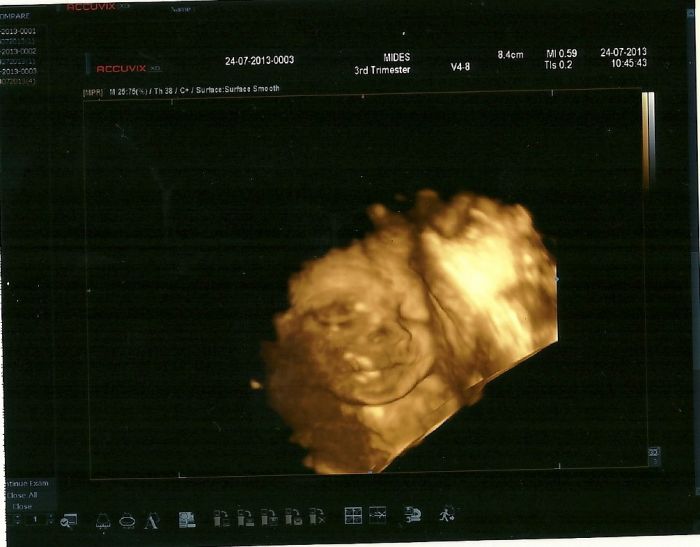

Jinak dneska začinám 6 měsíc a konečně se jí podařilo vyfotit našu holčičku :) tak nahrávám foto

no my už jsme napůl doktoři, když jsme to uhodly:) Fotka je krááásnáááá, holčičku závidííím